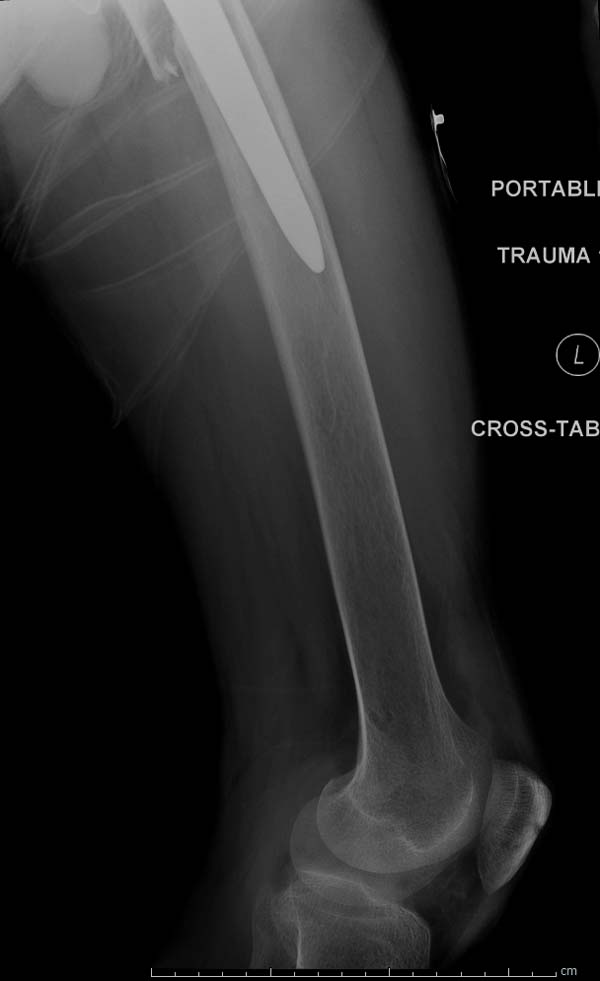

Больному 25 лет, транспортная травма. С детства хроническая почечная

недостаточность, постоянный гемодиализ, находится в листе ожидания на

пересадку почки. Около 4 года назад автоавария с двухсторенним переломом

ацетабулум, которая слева закончилось тотальным протезированием.

Диагноз: переломы бедренных костей, перелом дистального плеча слева,

также неосложненный перелом на уровне грудных позвонков.

Имя     : 3 Periprosthetic IM nail Lt femur 2.jpg